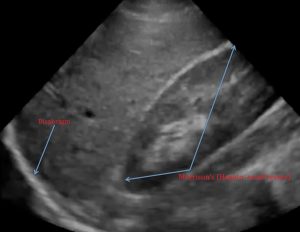

4.1 Ventana hepatorrenal (RUQ)

Modo: Convexo

Profundidad: 18–24 cm

Buscar:

-

Banda anecoica entre hígado y riñón

Líquido subhepático

Líquido suprahepático (hemotórax)

Es la ventana con mayor sensibilidad en trauma abdominal.

Receso hepatorrenal (Morrison)

La ecografía identifica líquido libre como colección anecoica en estos espacios.